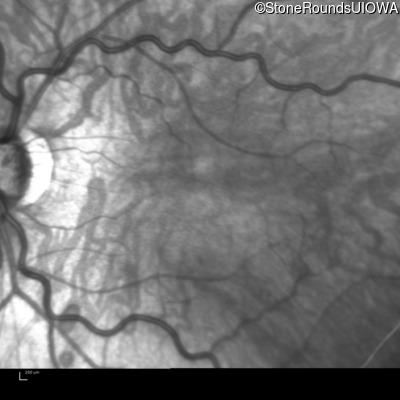

Age at visit: 26 years

This 26 year old man had significant myopia since childhood and uncorrectable reduction of acuity since his mid teens. Optic nerve abnormalities were noticed on a routine exam at age 5 and a diagnosis of Retinitis Pigmentosa was suggested. His medical history is also positive for profound hearing loss at birth and type 1 diabetes mellitus.